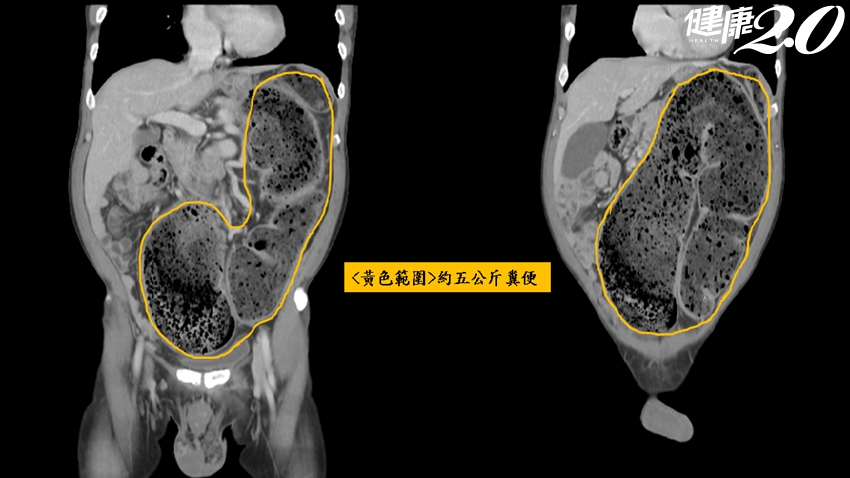

大腸直腸科醫師真辛苦,除了看病還得幫病人挖大便!一名58歲的男患者,大約20天都沒有解大便,因腹脹難受去醫院急診,醫師初步以肛門指檢發現有如石頭般的重物壓在骨盆腔肛門,因擔心是腫瘤造成腸阻塞,電腦斷層發現,患者乙狀結腸已塞滿5KG宿便,而且一路向上頂到了橫隔膜、胸腔甚至頂到心臟,醫師徒手幫他挖出宿便後,患者才獲得緩解。

▲患者體內約有5kg宿便,圖中可看出已頂到心臟。